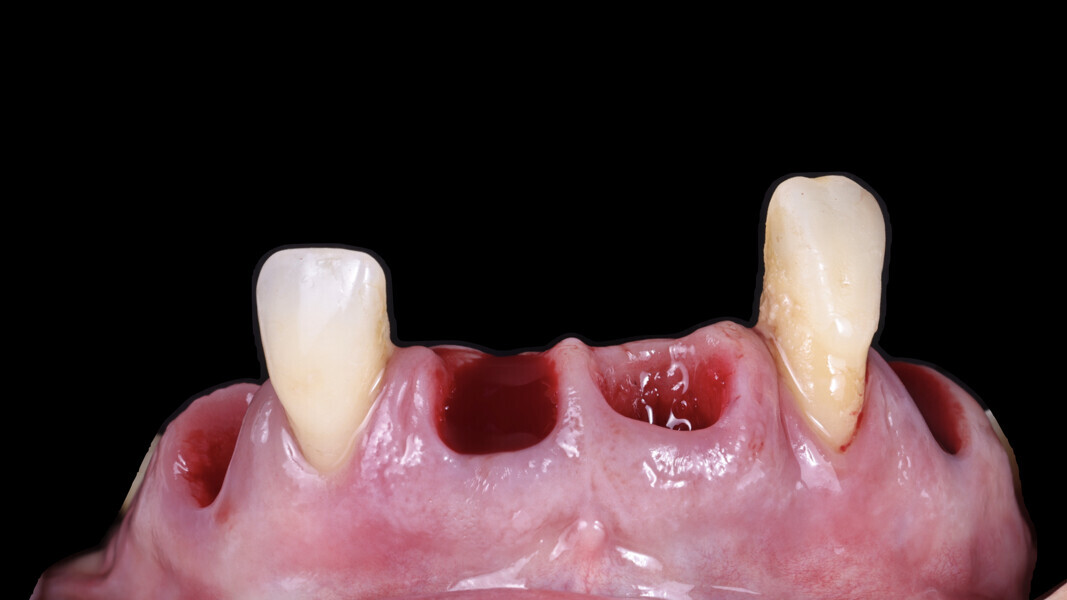

Fig. 4: Soft-tissue profile. We observed an excess of tissue overall except in the area of tooth #12, where a connective tissue graft (CTG) would be needed.

From an occlusal perspective, the patient exhibited both an excessive overjet and overbite (Fig. 3). However, her gingival architecture remained largely intact. Despite the presence of deep, untreatable periodontal pockets, there was minimal recession, thanks to her thick periodontal biotype (Fig. 4). This offered us an advantage. With careful planning and proper design, we were confident that we could preserve and slightly modify her gingival tissue to meet her aesthetic goals.